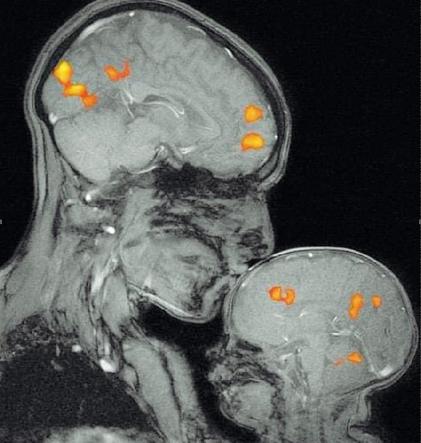

Come emozionare con una risoza: un’immagine pubblicata sulla rivista Neurology è riuscita a commuovere il web utilizzando uno strumento diagnostico. Si tratta della risoza funzionale eseguita sulla ricercatrice del Mit Rebecca Saxe mentre bacia sulla fronte suo figlio di pochi mesi. Dalla risoza è visibile la risposta emotiva del piccolo, evidenziata dalle aree cerebrali attivate dal gesto della madre. È una fotografia emblematica per il suo valore scientifico: questa e altre immagini sono la rappresentazione visiva dell’empatia. Nel suo libro The Emphatic Brain, la ricercatrice ha pubblicato molte foto analoghe – baci tra genitori e figli ma anche tra innamorati – evidenziando come questi gesti d’affetto facciano risuonare le stesse aree del cervello in entrambe le persone coinvolte.

Non solo ansia e depressione: le carenze di affetto causano anche il mal di testa

Una ricerca presentata da Vincenzo Guidetti, neuropsichiatra della Sapienza di Roma, al Congresso Internazionale sulle Cefalee di Stresa elenca il mal di testa tra i disturbi di internalizzazione derivati da carenze affettive nell’infanzia. Guidetti ha analizzato circa 60 studi condotti negli ultimi 5 anni. Gli strumenti di neurovisualizzazione hanno confermato quello che gli psicologi avevano intuito da tempo: i gesti di affetto dei genitori attivano specifiche aree del cervello legate allo sviluppo della coscienza. Più precisamente vengono attivate le aree frontali in entrambi i sessi, il solco temporale superiore di destra nelle femmine e la giunzione temporoparietale nei maschi. Le conclusioni della ricerca hanno evidenziato che nei bambini che soffrono di mal di testa la capacità di gestire le emozioni è alterata o carente.